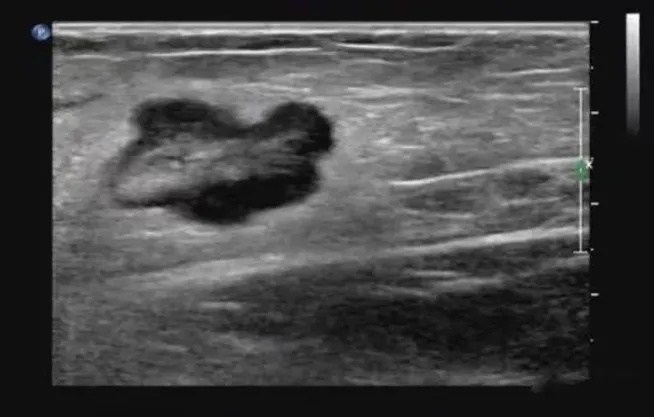

淋巴瘤

● 淋巴结不同程度肿大,多发,呈椭圆形、圆形,纵横比<2。

● 被膜清晰或不清晰,淋巴结之间可见融合。

● 皮质明显增厚呈低回声,不均匀,无液化、钙化;特征性回声改变为淋巴结内回声近似无回声的极低回声。

● 髓质变形或显示不清,或消失。

● 淋巴结内血流信号轻度或明显增多,分布杂乱;典型血流改变为淋巴结内血流信号丰富,红、蓝色血流信号充满整个淋巴结。

● 动脉血流速度加快,阻力指数正常或偏高。

淋巴瘤的血流信号在所有淋巴结中最为丰富。

淋巴结的内部回声一般表现为较均匀的低回声,当发生坏死时,其内部回声可相当低,接近无回声。